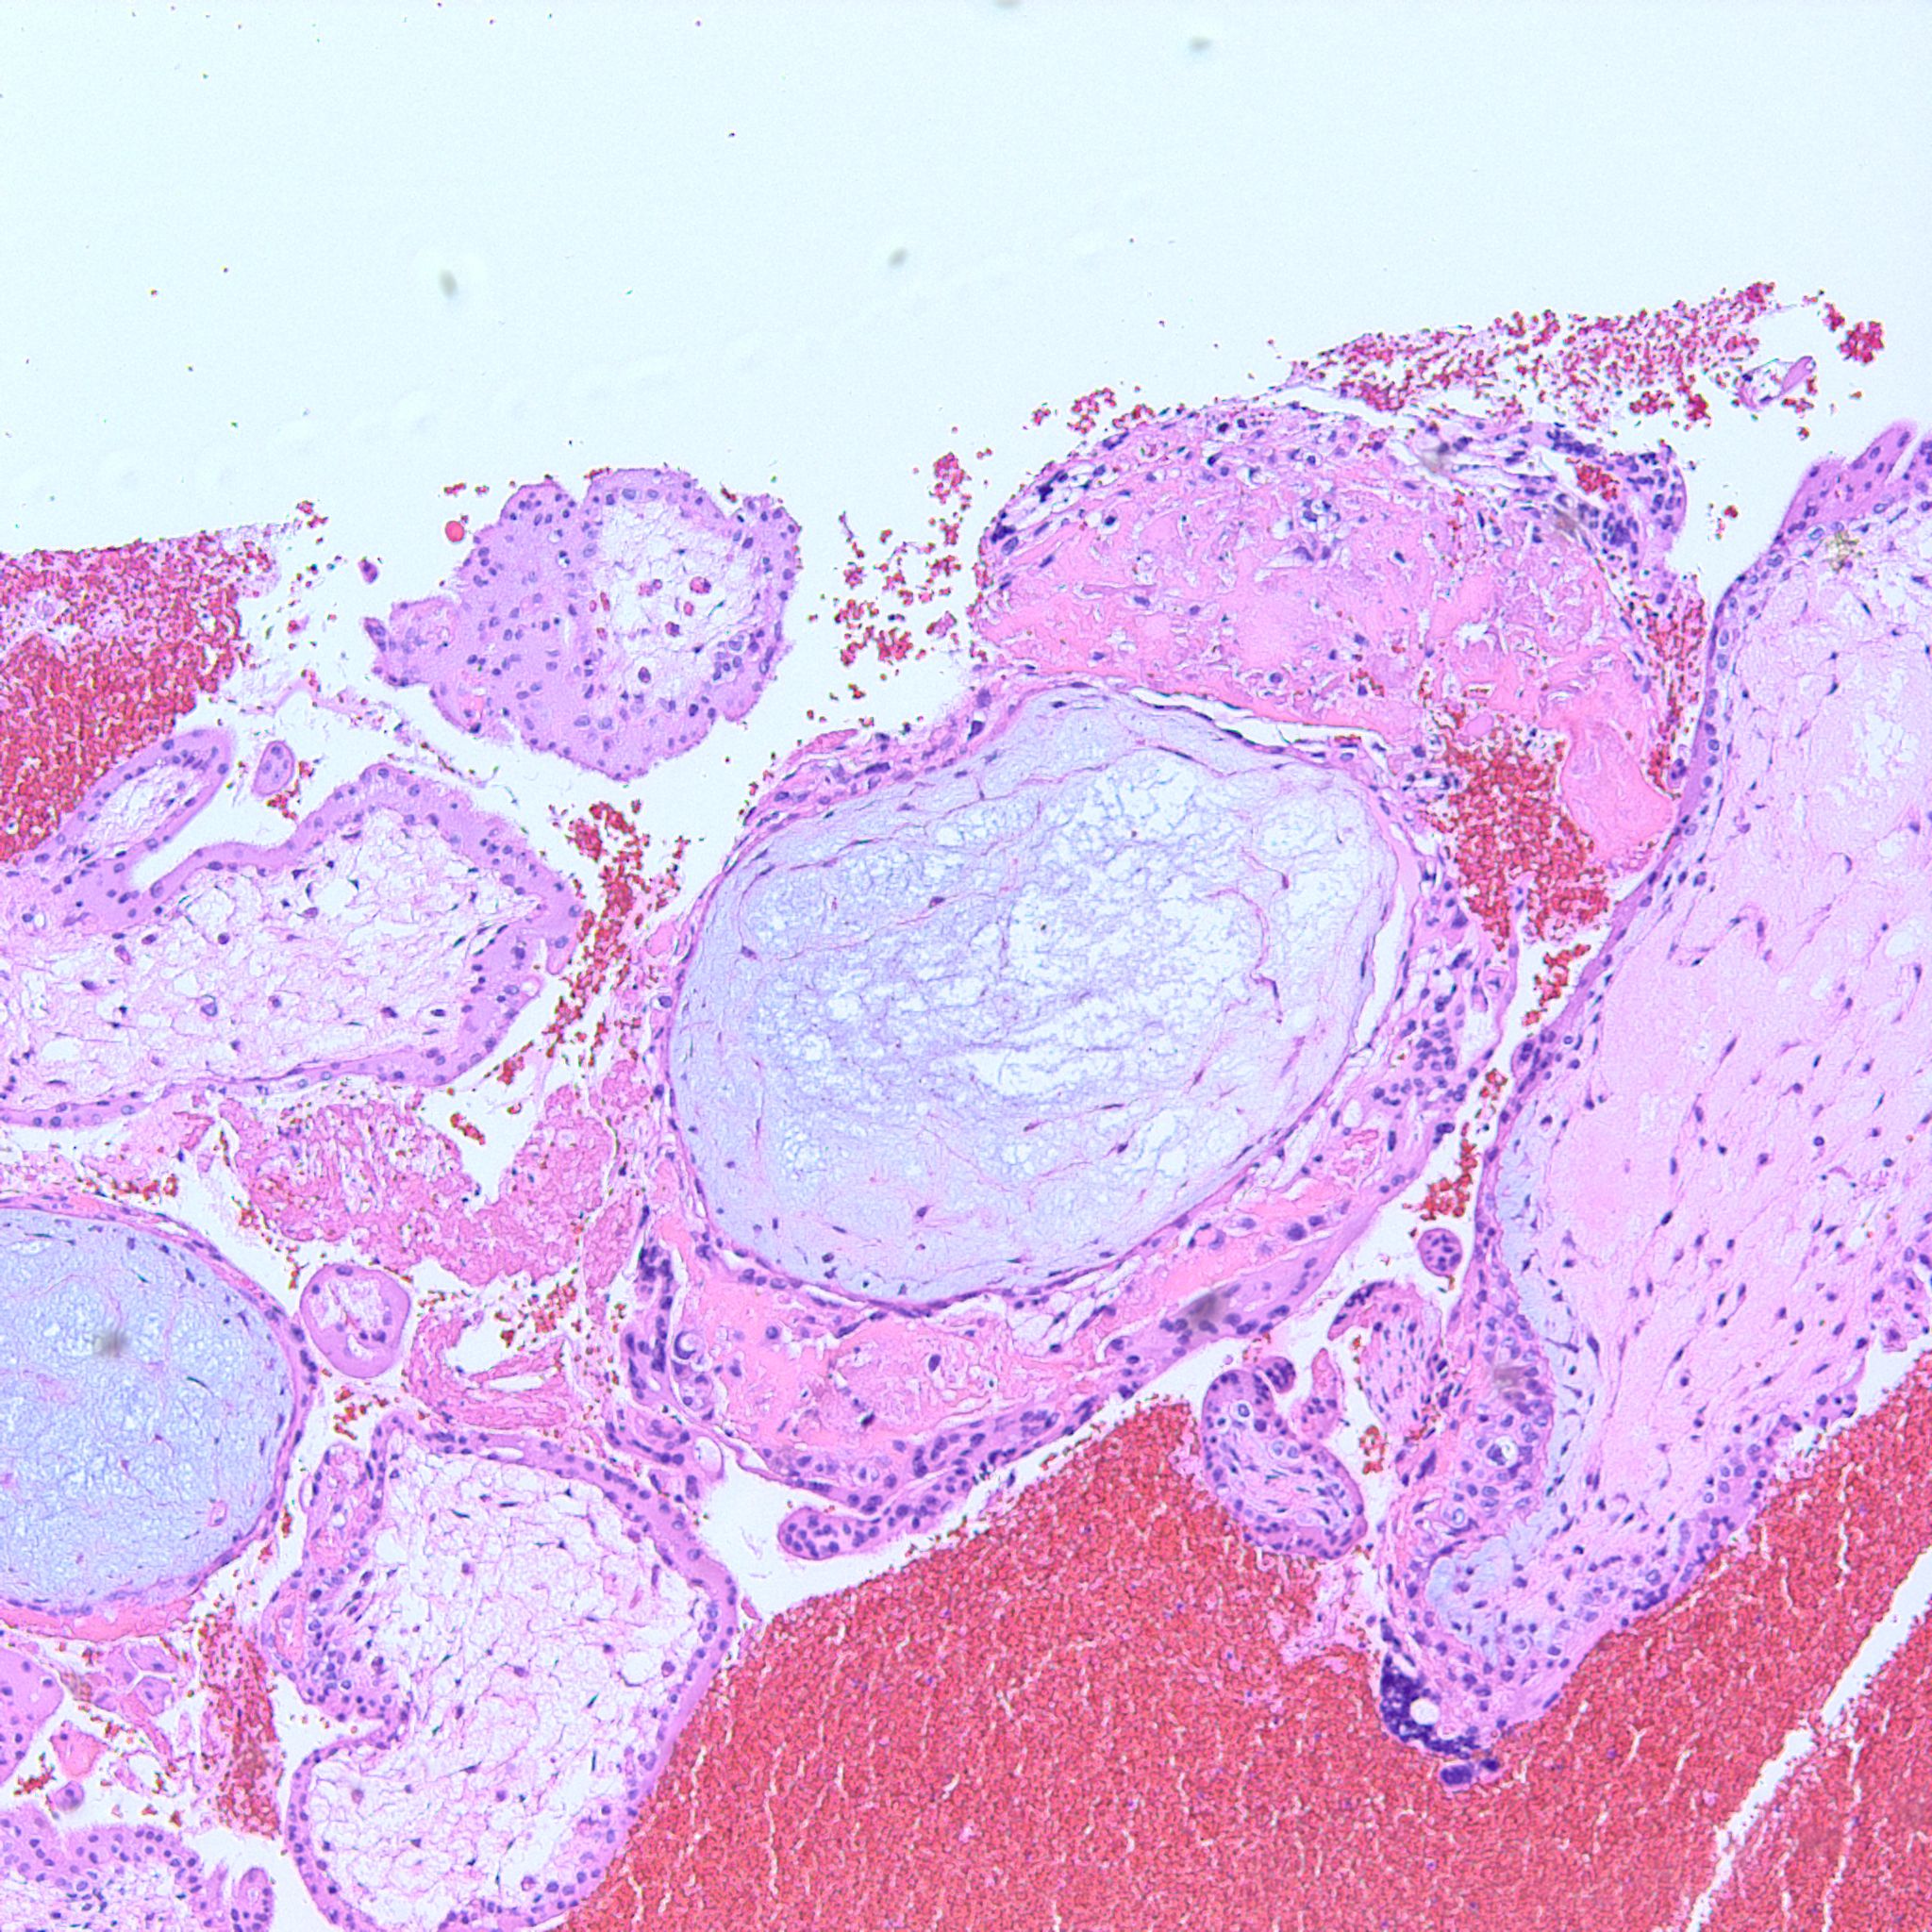

At low power we see throughout the specimen that numerous enlarged hydropic chorionic villi are present (circles).

As we can see, enlarged and hydropic chorionic villi are not especially difficult to find (circle). None of these villi however demonstrate trophoblastic inclusions. There are rare interspersed small chorionic villi (top left) however they are generally rare.

Some villi are so large and hydropic that a few have actually developed central cisterns, spaces within the center of the villi (space highlighted by horizontal lines).

This large hydropic villus with central cistern also demonstrates an important finding: the loss of polarity of the surrounding trophoblasts with circumferential proliferation of variably atypical trophoblastic cells (arrows).